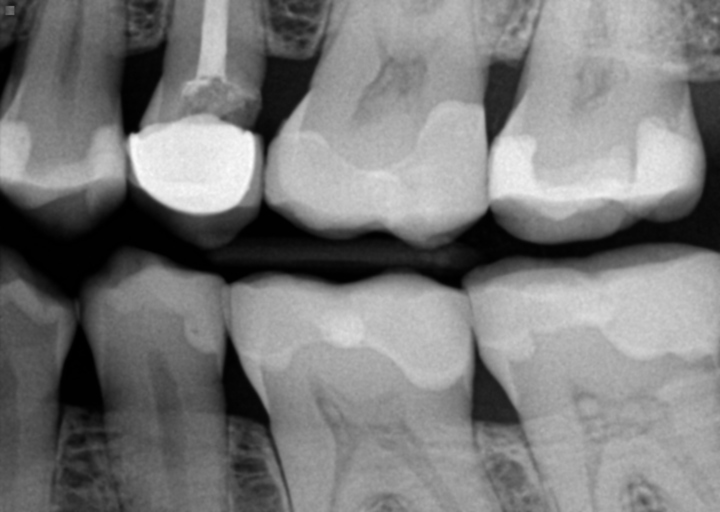

Cavity under crown or ill fitted crown?

I have received conflicting opinions on a tooth: one dentist said it is cavity under the crown and treatment could be crown lengthening/dental implant while other dentist said there is no cavity, it's just ill fitted crown. Is this something we can...